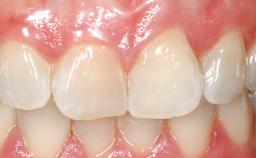

A 33-year-old female patient presented with an upper left central incisor that required extraction after a failed endodontic therapy. The tooth had been traumatized when the patient was a teenager and had undergone several endodontic treatments, including two apicectomy procedures. The patient was in good health and did not smoke. Clinical examination showed that the patient had a high lip line. In full smile, the gingival margins of the upper teeth were visible to the first molars. The gingival margins of central incisors 11 and 21 were only just showing. Examination of tooth 21 confirmed that the tooth was mobile and had hypererupted by 1 mm.

Prosthesis Type FDP

Mesio-Distal Space Symmetry +/- 1 mm of contra-lateral tooth